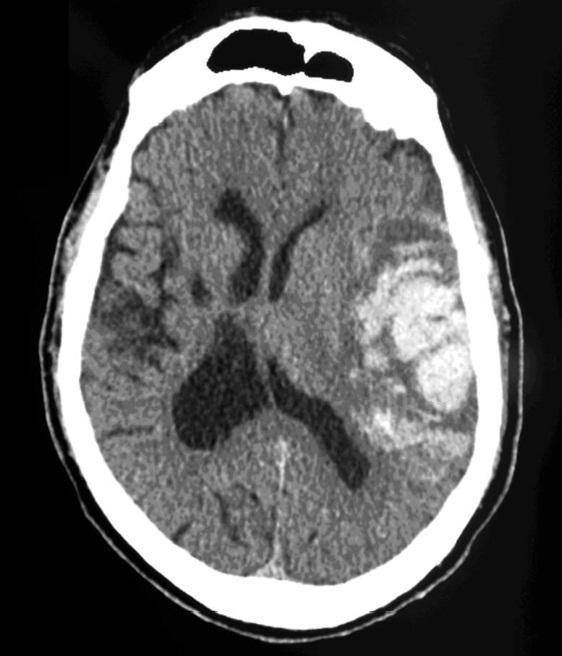

Massive ICH